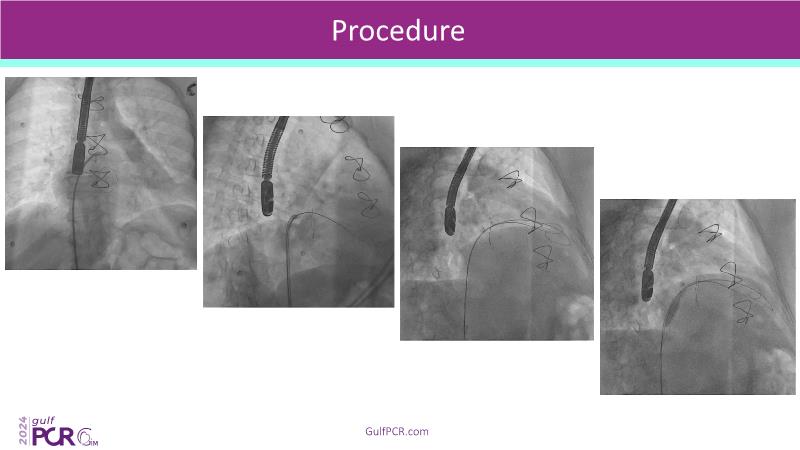

Stay ahead in TAVI innovation by exploring the advanced balloon-expandable Myval THV series. This session highlights the latest clinical data, optimal sizing and implantation techniques, and valuable real-world insights, including long-term follow-up results.

- To understand the best practices for Myval sizing and implantation technique for best outcomes